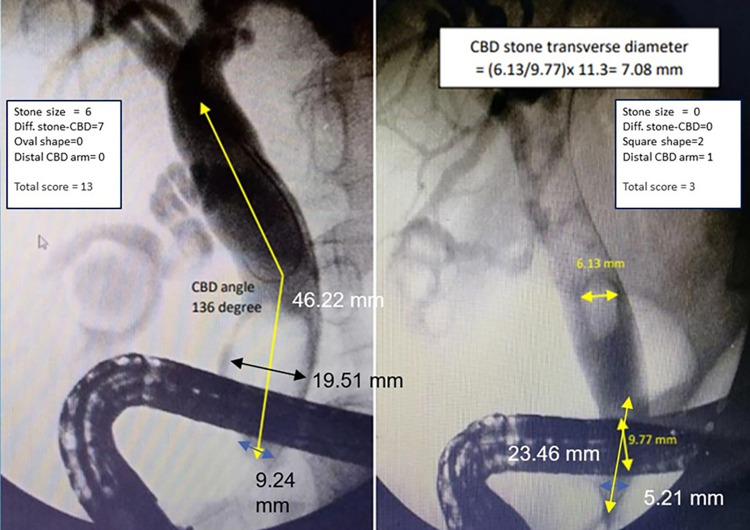

This study documented and categorized clinical parameters into four groups: general characteristics, intraoperative data, endoscopic procedure, and adverse events. 1) General characteristics include age, gender, body mass index (BMI), underlying disease, acute cholangitis, and previous cholecystectomy. 2)Intraoperative information includes endoscopic findings such as: periampulla diverticulum, cholangiographic findings such as: mid-CBD diameter and, distal CBD diameter that was measured at 1 cm proximal to the main ampulla’s orifice [ref. 13]. The CBD angle is defined as the angle formed by the CBD between 1 cm below the bifurcation and 1 cm above the papilla [ref. 14–ref. 16]. The distal CBD arm is defined as the distance between the ampullary orifice to the distal CBD angulation point, the longitudinal diameter and transverse diameter of stone at the point of maximum diameter. The difference of stone to distal CBD diameter was calculated by CBD stone diameter (mm) minus the distal CBD diameter (mm). The CBD stone and CBD diameter were corrected for radiograph magnification by multiplying the measured diameter of CBD or stone with the ratio of the actual and measured diameters of the duodenoscope on cholangiography [ref. 17]. The stone/CBD ratio, the number of stones, the shape of stone was categorized into oval, round, squared, or fragmented shape, and impacted stone. 3) Endoscopic procedures include endoscopic sphincterotomy (EST), stone extraction by balloon and/or basket, endoscopic papillary balloon dilation (EPBD), mechanical lithotripsy (ML), and stent use. 4) Adverse events include post-ERCP pancreatitis and bleeding in 24 hours after the procedure.

In the reduced model, a total of four predictors were used. A score was provided for each final predictor based on the logistic regression coefficient of each item. For predicted applicability, the logistic coefficient of each predictor was divided by the model’s lowest coefficient and rounded to the nearest non-decimal integer. The model achieves a total score ranging from 0 to 16 with a cut-off of 5 to achieve high specificity for suggesting EPLBD in addition to standard procedures. Positive predictive value (PPV) and likelihood ratio of positive value were computed for each score category to determine the patients’ average risk.

A calibration plot revealed that the score predicted the probability of EPLBD requirement, and the observed risk of EPLBD requirement in the derivation cohort concomitantly increased as the score increased (Fig 3). We selected a cut point value at 5 because of high specificity (94.74%) and sensitivity (72.15%), allowing for the inclusion of individuals with more difficult CBD stones. A score of 5 or higher will likely require EPLBD or further procedures. It was suggested that patients should be referred to a hospital with the necessary equipment to dilate CBD or to make the stones smaller. (Fig 4).

This study demonstrates that a simple tool, based on stone and CBD-related parameters, was able to stratify the risk of difficult CBD stone endoscopic removal. In particular, the DCSS score was acceptable for evaluating additional procedures required among CBD stone patients who underwent endoscopic treatment. Our final model selected four predictors: stone diameter, the difference between stone and distal CBD diameter, stone shape, and distal CBD arm length.

Many publications report stones larger than 15 millimeters in diameter would predict the probability of unsuccessful stone removal [ref. 14–ref. 16]. While stones less than 10 millimeters decrease the probability of a failed stone removal. Hence, the size of the stone has been categorized as less than 10 mm, 10–15 mm, and more than 15 mm. This predictor is a strong indication for the use of EPLBD, which indicates difficult CBD stone removal. The larger transverse diameter stone makes it difficult to remove. Because it may be difficult to grasp while applying basket retraction or passing the stone through a small orifice during swiped balloon, therefore, removing the large stone may require using EPLBD or its fragmentation before extraction.

The difference in diameter between the CBD stone and the distal bile duct, which exceeds 2 mm, was a strong predictor for required EPLBD. We categorized the difference in diameter between the CBD stone and the distal bile duct into two groups based on Sharma et al., implying that stones wider than the distal CBD diameter by more than 2 mm, regardless of stone size, may require an additional stone removal procedure [ref. 19]. Furthermore, and the cut-off point of the difference in diameter, which has a high specificity to discriminate between non-difficult CBD stones and the difficult groups in our data, hence the cut-off point of the difference in diameter at two milli-meters was reasonably considered as our predictor.